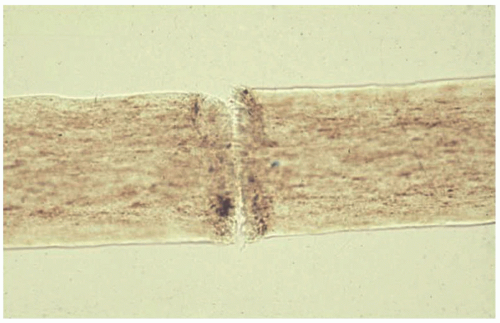

Each node is formed by cortical fiber separation and fraying of the hair shaft in a manner analogous to the bristles of two paint brushes being pushed together (Figure 14-2).